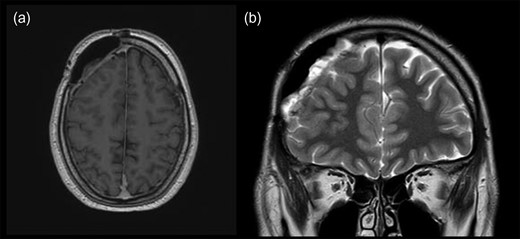

The patient was transferred to the hematology department for further diagnostic procedures. Upon analysis no pathological findings were found. After consultation R-CHOP and intrathecal methotrexate protocol was chosen. The patient was administered four cycles of R-CHOP and intrathecal methotrexate. Four months afterwards, MRI and neurosurgical control were performed. MRI revealed satisfying postoperative result without any new intracranial masses (Fig. 3).

MRI scans of brain, 4 months postoperatively, revealing no recurrence of lymphoma in (a) transverse and (b) coronal plain.